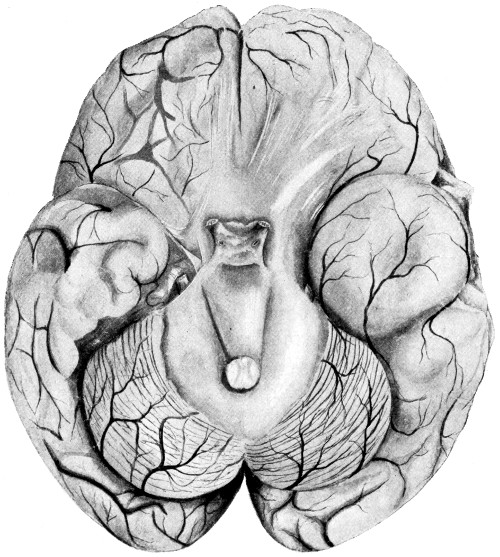

76. To illustrate the pressure effects of a temporo-sphenoidal abscess 257

77. A cerebellar abscess 259

78. To illustrate diagrammatically the symptoms observed in cerebellar abscess formation (after Luciani) 261

79. The exposure of a temporo-sphenoidal abscess 265